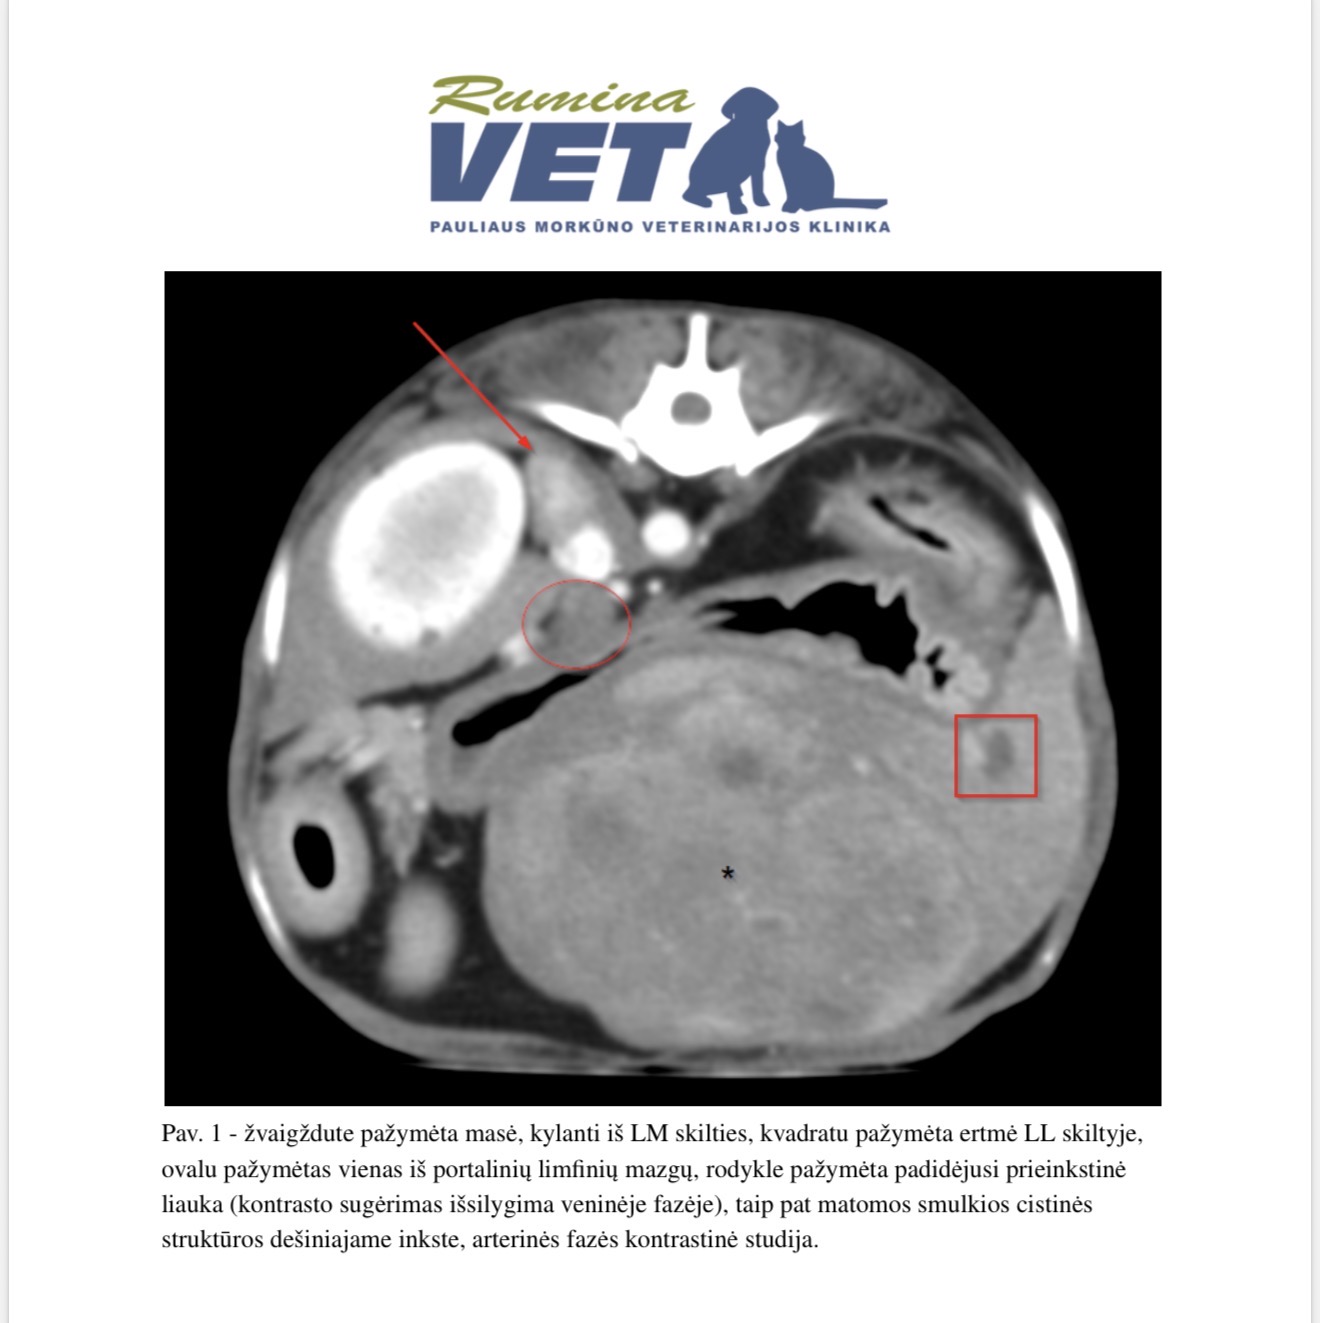

Į mane kreipėsi Gučis, kuriam buvo diagnozuotas kepenų vėžys. Šeimininkai labai bijojo, tačiau tikėjimas, pasitikėjimas ir didelis noras kovoti nugalėjo baimę.

Ir šiandien – sėkmė. Pavyko atlikti sėkmingą operaciją: pašalinta dalis kepenų kartu su visu onkologiniu židiniu. Metastazių nestebima. O veide – šypsena.